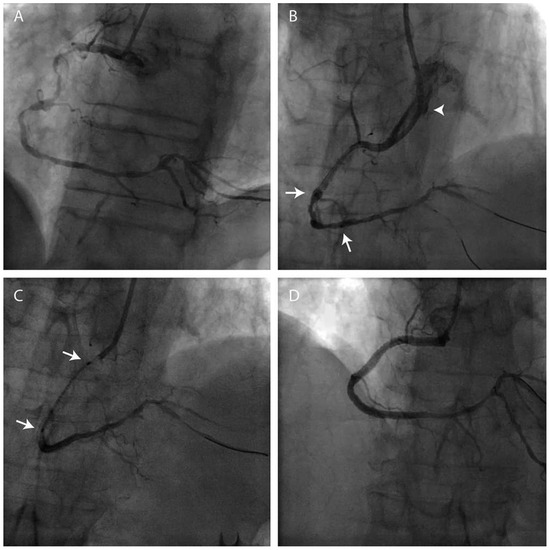

Case report. A 63-year-old hypertensive male presented with atypical chest discomfort and breathlessness on exertion [...]